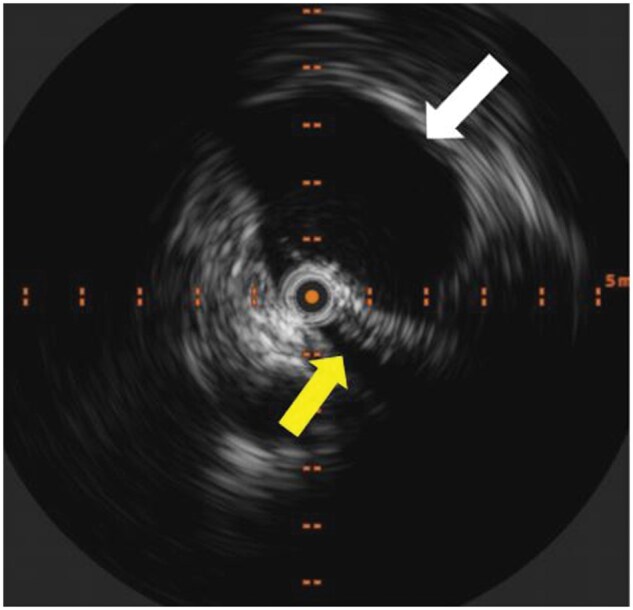

May-Thurner生理(MTP)可导致各种充血综合征,由于右髂总动脉(RCIA)压迫左髂总静脉(LCIV)。这种压迫可能导致通过腰静脉的静脉回流,导致脊髓硬膜外静脉丛(EVP)充血,这可能导致顽固性头痛。本病例报告详细介绍了一例伴有MTP的严重难治性新发持续性头痛患者的临床过程,该患者接受了腰升静脉(ALV)栓塞术。患者为59岁女性,每日持续性头痛3年,多次偏头痛预防治疗和微创手术均无效。影像学研究显示RCIA对LCIV有明显压迫,ALV血流逆行,EVP充血。患者接受了ALV栓塞治疗,症状明显缓解。在22个月的随访中,头痛严重程度降低了80%,患者不再需要常规的头痛药物。此外,通过性腺静脉栓塞治疗相关盆腔充血综合征解决了长期相关的盆腔疼痛和压力。本病例强调了静脉充血在难治性头痛综合征中的作用,并强调了靶向静脉干预的潜力,如栓塞,在其管理中。研究结果扩展了将静脉压迫综合征与头痛病理生理联系起来的新证据,并支持探索干预策略作为选定患者的可行治疗选择。需要进一步的研究来验证这些发现,并为临床实践建立循证指南。

May-Thurner physiology (MTP) can lead to various congestion syndromes due to compression of the left common iliac vein (LCIV) by the right common iliac artery (RCIA). This compression may result in venous reflux through the lumbar vein, leading to congestion of the spinal epidural venous plexus (EVP), which could contribute to refractory headaches. This case report details the clinical course of a patient with severe refractory new daily persistent headache associated with MTP who underwent ascending lumbar vein (ALV) embolization. The patient is a 59-year-old female with a 3-year history of daily persistent headache which failed multiple migraine prevention therapies and minimally invasive procedures. Imaging studies revealed significant LCIV compression by the RCIA, retrograde ALV flow, and EVP congestion. The patient underwent ALV embolization, resulting in significant symptomatic relief. At the 22-month follow-up, headache severity reduced by 80%, with the patient no longer requiring routine headache medications. Additionally, treatment of associated pelvic congestion syndrome through gonadal vein embolization resolved longstanding associated pelvic pain and pressure. This case highlights the role of venous congestion in refractory headache syndromes and underscores the potential of targeted venous interventions, such as embolization, in their management. The findings expand on emerging evidence linking venous compression syndromes to headache pathophysiology and support exploring interventional strategies as viable treatment options for selected patients. Further research is needed to validate these findings and establish evidence-based guidelines for clinical practice.